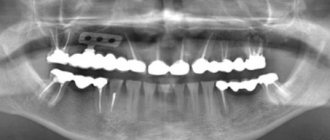

Ортопантомограмма — панорамный снимок зубов950